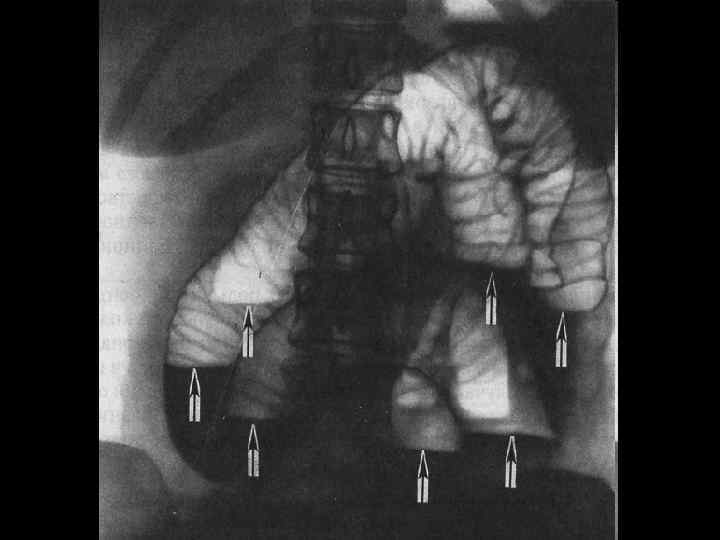

Острая кишечная непроходимость • При обтурации боль схваткообразная, при странгуляции наряду со схватками – постоянная (часто явления шока) • Клиника зависит от уровня непроходимости. • Характерны задержка стула, многократная рвота. • При проведении обзорной рентгеноскопии обнаруживаются чаши Клойбера. • В клинической картине: боль, часто сопровождающаяся кровотечением, непостоянной диареей. • На рентгенограмме: симптом «отпечатки пальцев» , часто поражение селезеночного угла

Рентгенограмма брюшной полости при тонкокишечной непроходимости. Хорошо видны спиралевидные складки слизистой оболочки, занимающие весь поперечник кишки (указаны стрелками)

Рентгенограмма брюшной полости при толстокишечной непроходимости. Видны гаустры (указаны стрелками), которые занимают лишь часть поперечника кишки